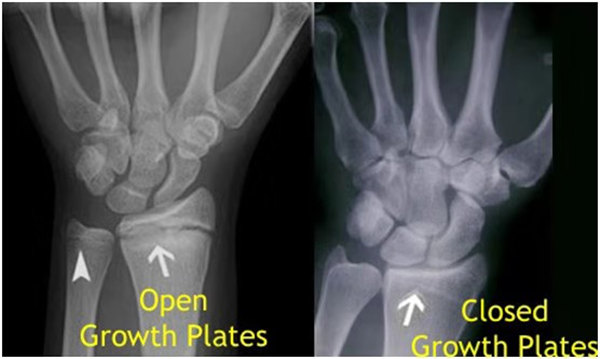

我們都知道,人體的高矮是由骨骼的生長發育決定的,特別是下肢長骨。長骨呈長管狀,在長骨的兩端有一種專管骨骼生長的骺軟骨,它與干骺端之間有一盤狀軟骨結構稱為骺板(線),在幼兒的X光片上表現為一條較寬的透光帶。 (見下圖)

未成年時隨著年齡的增加骺軟骨端不斷骨化,骨骼就不斷增長。當骨骺線完全閉合時骨骼就停止生長,個子也就不再增長了。一般骨骺端完全閉合的年齡是18~20歲左右。